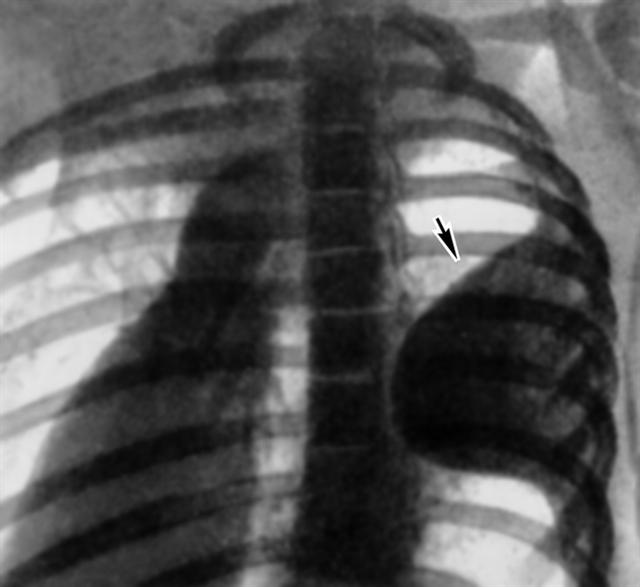

Рис. 5. Рентгенограмма органов грудной клетки больного с осумкованным левосторонним пристеночным плевритом (левая косая проекция): к грудной стенке прилежит интенсивная тень выпота (указана стрелкой).